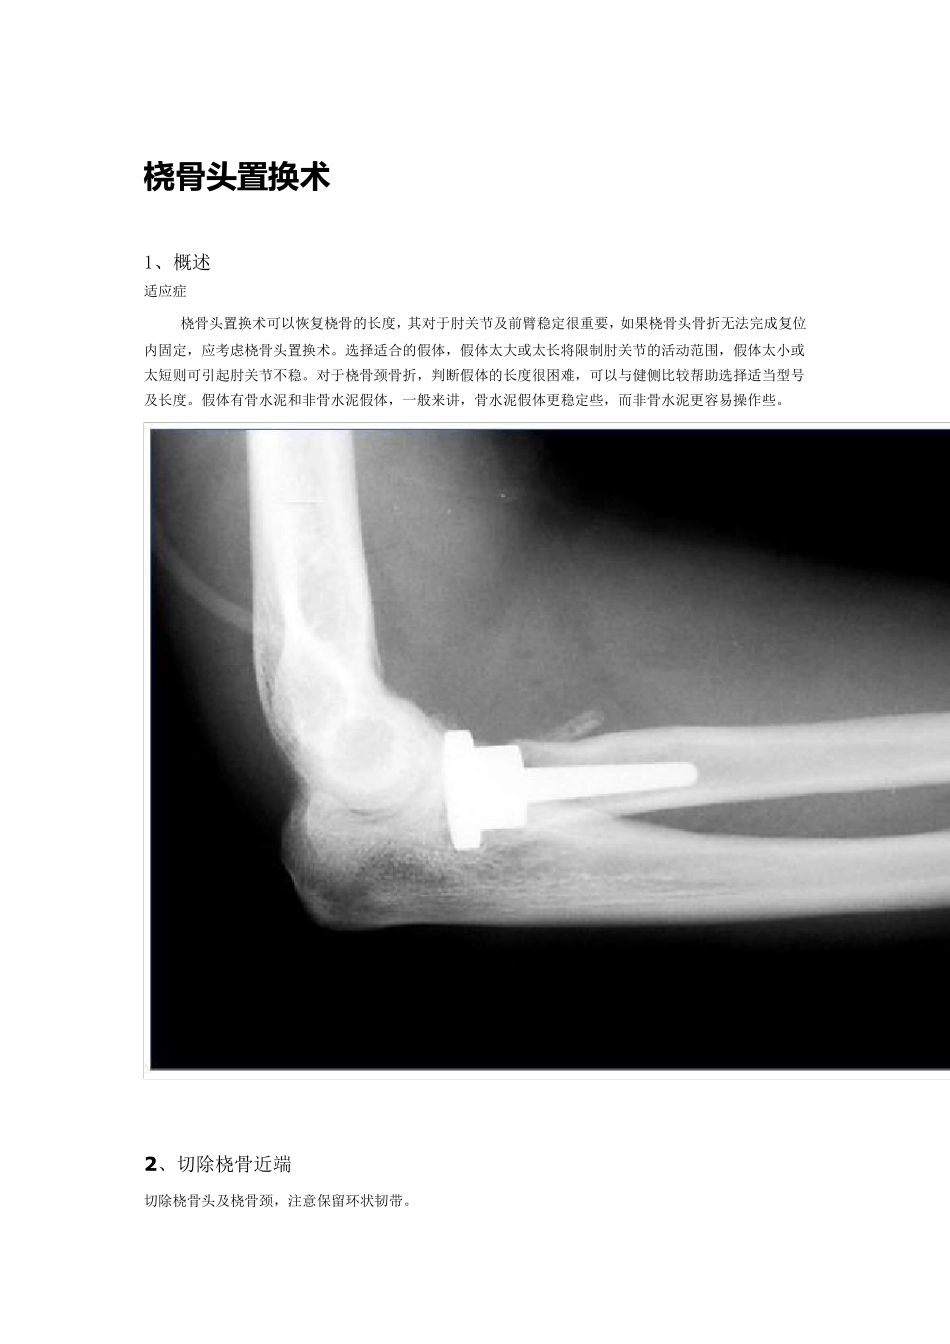

桡 骨 头置换术 1、概述 适应症 桡骨头置换术可以恢复桡骨的长度,其对于肘关节及前臂稳定很重要,如果桡骨头骨折无法完成复位内固定,应考虑桡骨头置换术。选择适合的假体,假体太大或太长将限制肘关节的活动范围,假体太小或太短则可引起肘关节不稳。对于桡骨颈骨折,判断假体的长度很困难,可以与健侧比较帮助选择适当型号及长度。假体有骨水泥和非骨水泥假体,一般来讲,骨水泥假体更稳定些,而非骨水泥更容易操作些。 2 、切除桡骨近端 切除桡骨头及桡骨颈,注意保留环状韧带。 修整桡骨颈残端 3 、置换 开通髓腔,用适合的假体髓腔锉扩髓。 插入假体,评估假体长度及稳定性。 避免过长或过短,评估:桡骨头假体关节面应与尺骨冠状突外侧缘关节面平行一致,或稍短于冠状突关节面。长度可以通过与健侧对比明确。 最后评估:检查假体在屈、伸、旋前、旋后时肘关节的稳定性,如果关节僵硬或不稳,更换假体型号,最后修复环状韧带。